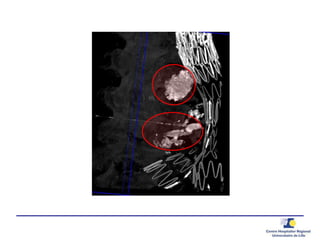

Ponction translombaire –

embolisation directe

Ponction

Anévrysmographie